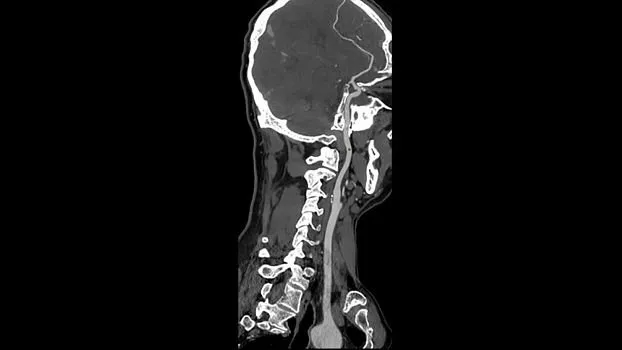

Клинические изображения

Технология TrueFidelity

Revolution Ascend поддерживает технологию TrueFidelity**, которая реконструирует изображения с помощью алгоритмов глубокого обучения. Она обеспечивает глубокую детализацию, естественную текстуру, высокую контрастность и четкость изображений. TrueFidelity генерирует изображения с помощью алгоритмов искусственного интеллекта. Это позволяет, с одной стороны, использовать низкую лучевую нагрузку, как при итеративной реконструкции, а с другой стороны, получать изображения, не уступающие по качеству методу фильтрованных обратных проекций.